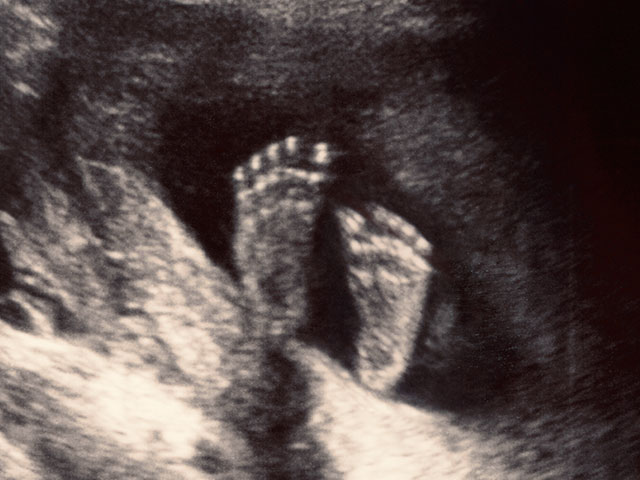

According to an article in The Harvard Journal of Law and Public Policy, law student Joshua Craddock argues that a person becomes a human being at the point of conception, and from that moment forward is entitled to protection under the law.

Craddock writes, "The preborn are members of the human species from the moment of fertilization. Therefore, the Fourteenth Amendment protects the preborn. If one concedes the minor premise (that preborn humans are members of the human species), all that must be demonstrated is that the term 'person,' in its original public meaning at the time of the Fourteenth Amendment's adoption, applied to all members of the human species."

Craddock asserts that the intent of the Fourteenth Amendment was to include the protection of the unborn. "A general consensus treated preborn human beings as 'persons,'" he says. "The preborn were included within the public meaning of the term 'person' at the time the Fourteenth Amendment was adopted."